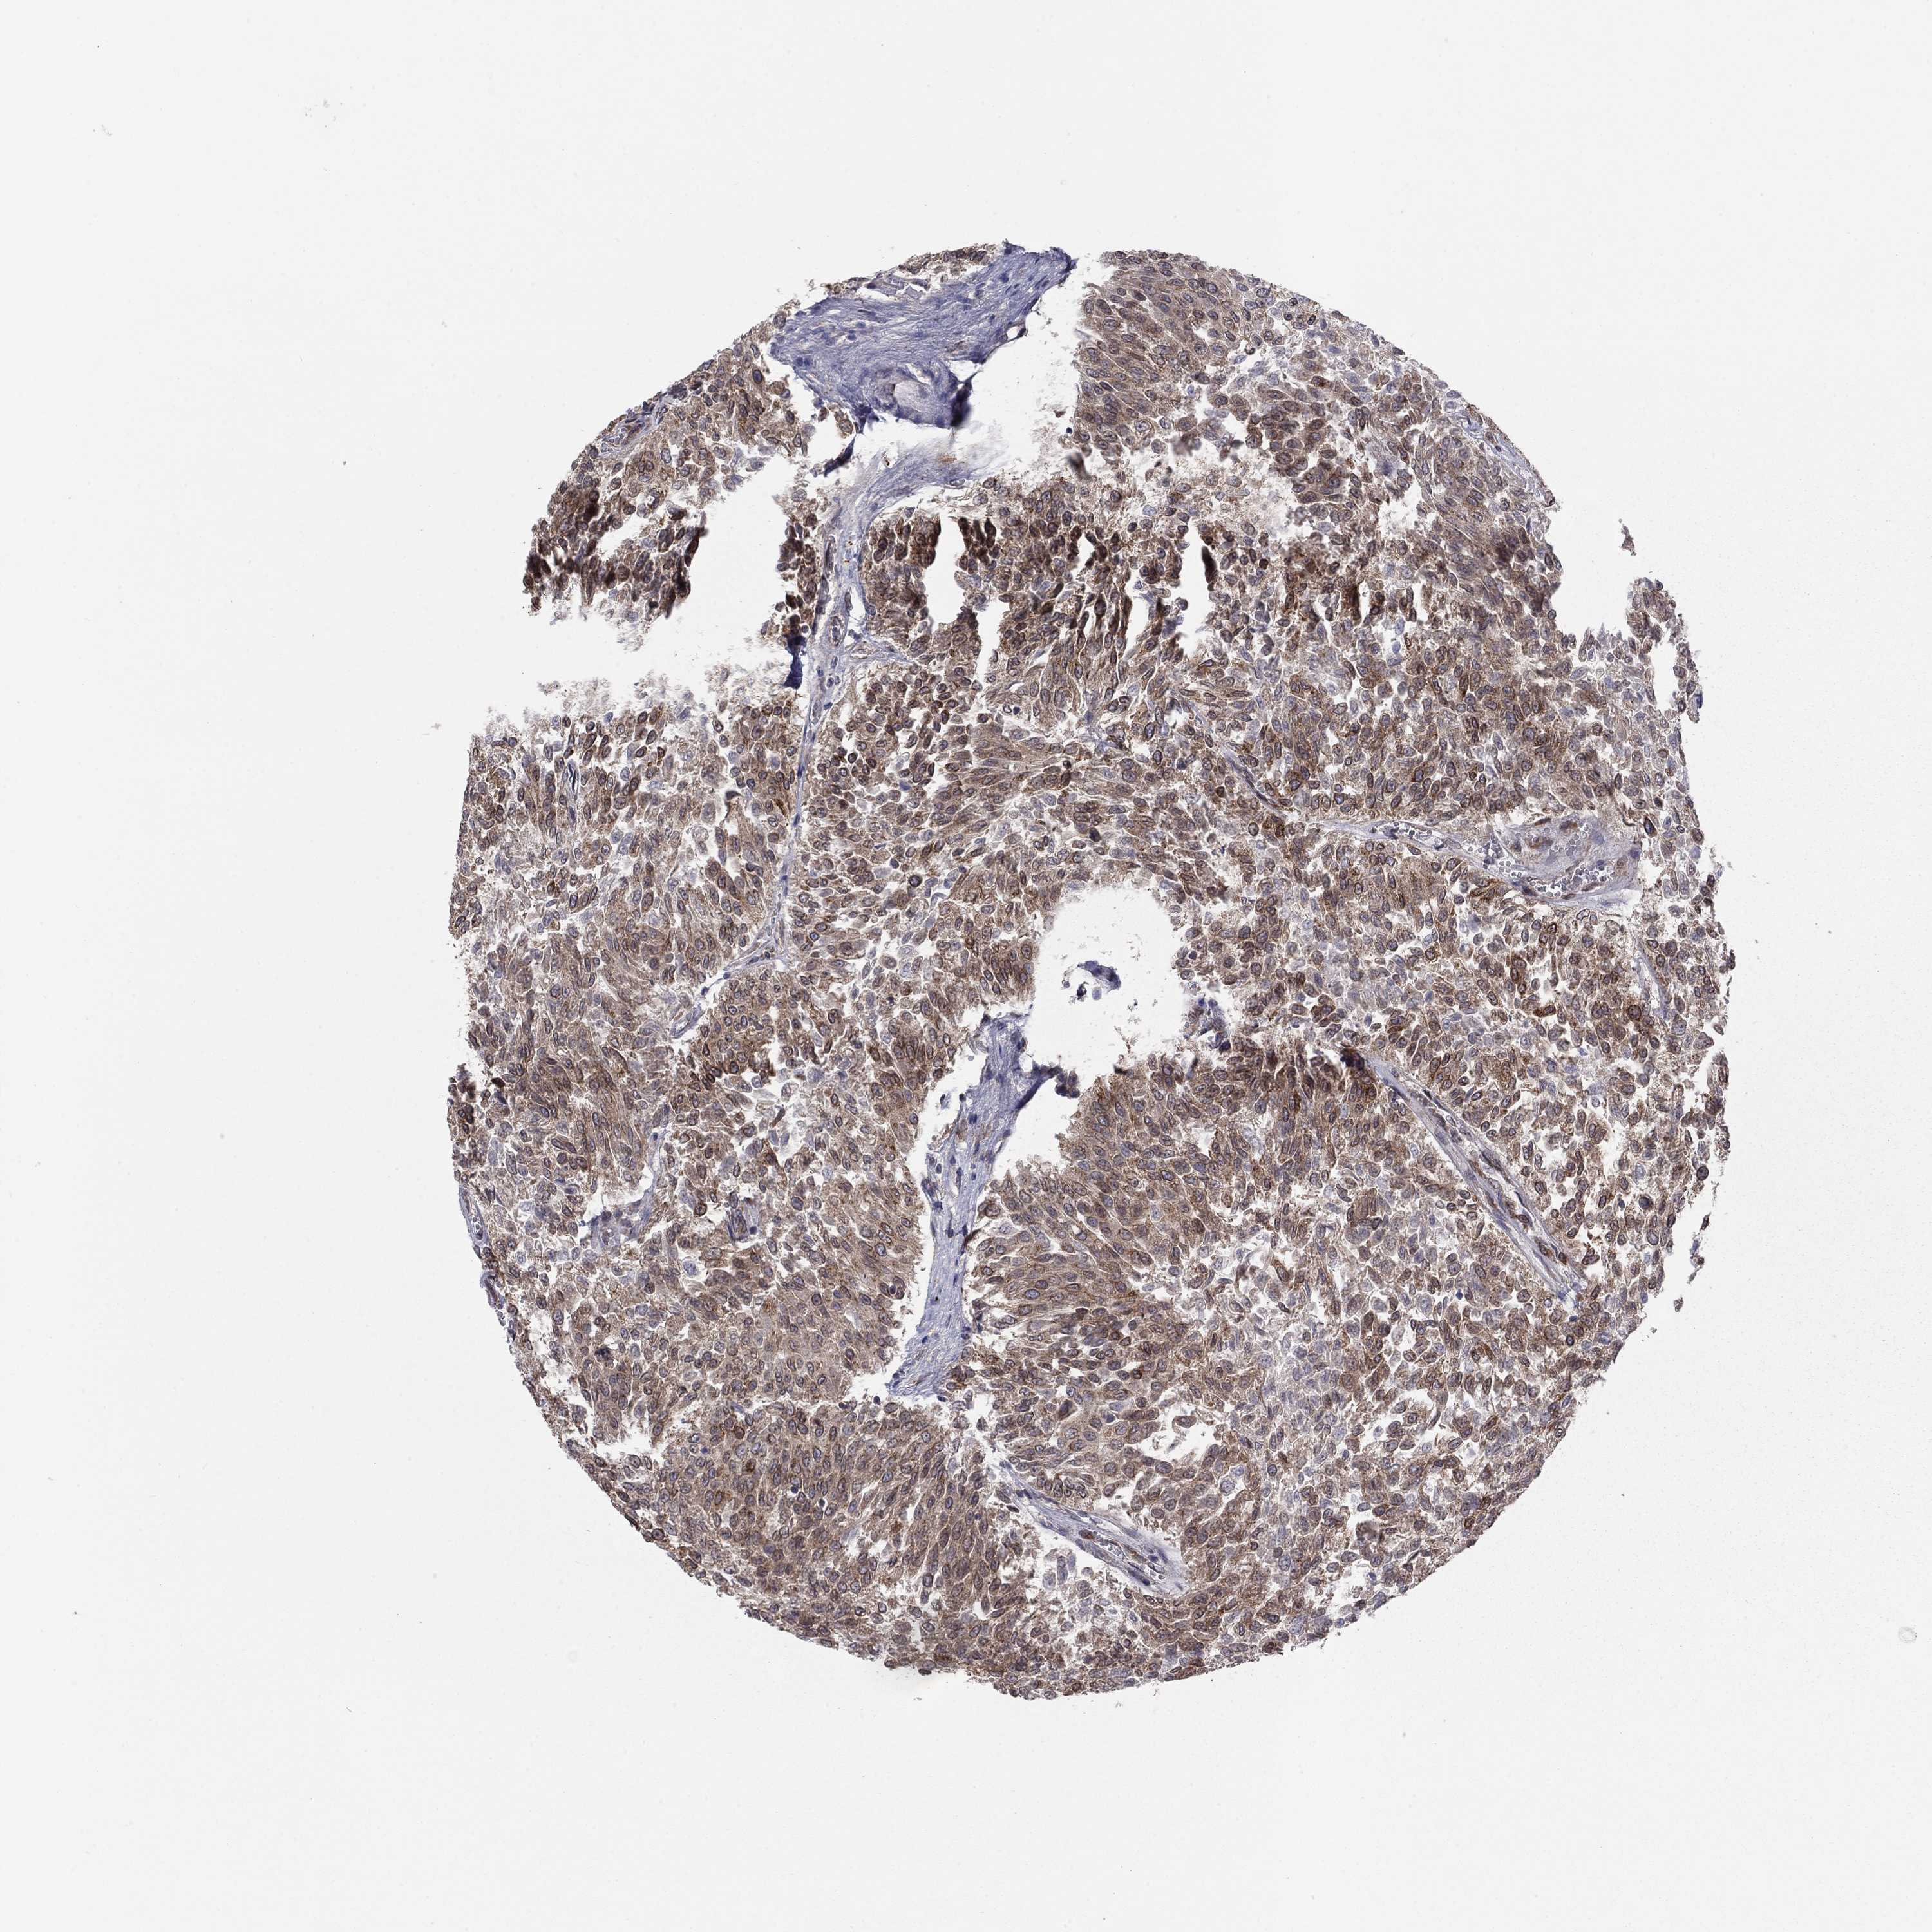

UROTHELIAL CANCER - Protein expressioni

A mouse-over function shows sample information and annotation data. Click on an image to view it in a full screen mode. Samples can be filtered based on level of antibody staining by selecting one or several of the following categories: high, medium, low and not detected. The assay and annotation is described here.

Note that samples used for immunohistochemistry by the Human Protein Atlas do not correspond to samples in the TCGA dataset.

Antibody stainingi

Antibody staining in the annotated cell types in the current human tissue is reported as not detected, low, medium, or high, based on conventional immunohistochemistry profiling in selected tissues. This score is based on the combination of the staining intensity and fraction of stained cells.

Each image is clickable and will lead to virtual microscopy that enables deeper exploration of all samples and also displays staining intensity scores, fraction scores and subcellular localization as well as patient and tissue information for each sample.

Antibody HPA076194

Staining

High

Medium

Low

Not detected

Intensity

Strong

Moderate

Weak

Negative

Quantity

>75%

75%-25%

<25%

None

Location

Nuclear

Cytoplasmic/membranous

Cytoplasmic/membranous,nuclear

Urothelial carcinoma, High grade

Urothelial carcinoma, Low grade